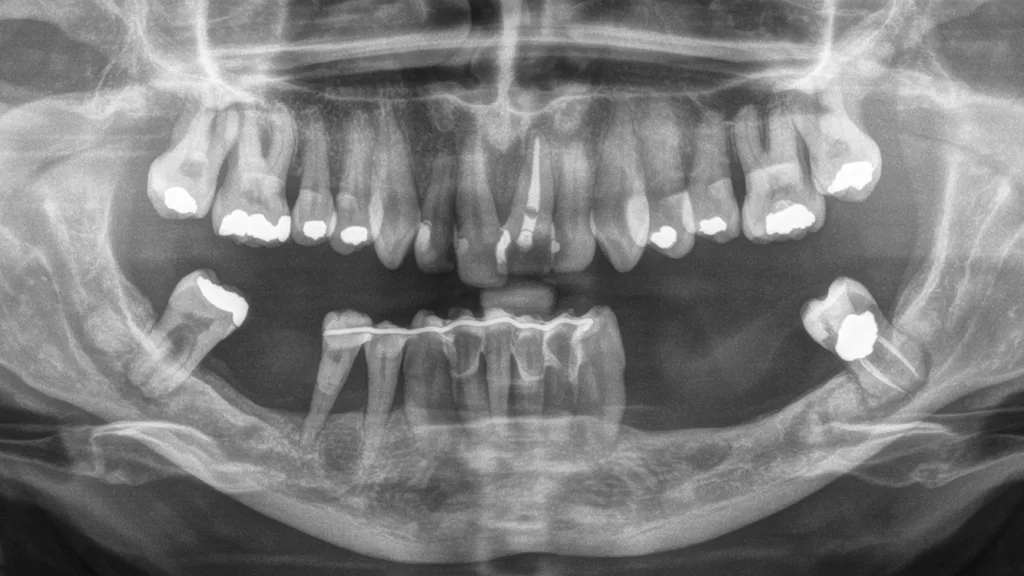

Im Gegensatz dazu existieren eine Reihe seltener Syndrome, bei denen betroffene Personen unabhängig von klassischen Risikofaktoren eine schwere parodontale Destruktion entwickeln. Seltene Syndrome sind (meist) genetisch bedingte Erkrankungen, die durch eine charakteristische Kombination klinischer Symptome gekennzeichnet sind und gemäß europäischer Definition eine Prävalenz von weniger als 1 pro 2.000 Personen aufweisen. In der Parodontologie ist eines der bekanntesten Beispiele das autosomal-rezessiv vererbte Papillon-Lefèvre-Syndrom, das durch eine rasch-progrediente Parodontitis im Kindesalter sowie durch palmoplantare Hyperkeratosen der Hände und Füße gekennzeichnet ist; ursächlich sind Mutationen im Cathepsin-C-(CTSC-)Gen (Abb. 1, Abb. 2).

Das Papillon-Lefèvre-Syndrom (PLS) ist, wenn alle Symptome ausgeprägt sind, durch die generalisierte Parodontitis im Milchgebiss in Kombination mit palmoplantaren Hyperkeratosen klinisch leicht zu diagnostizieren [12]. Allerdings gibt es auch Fälle, in denen nur die Hautveränderungen oder die Parodontitis auftreten. Durch die autosomal-rezessive Vererbung tritt PLS nur auf, wenn beide Allele – das mütterlich und das väterlich vererbte Allel – eines Gens defekt sind. Das können homozygote Mutationen sein, also zwei idente Mutationen, wenn die Eltern einen Verwandtschaftsgrad aufweisen, oder auch unterschiedliche Mutationen im Cathepsin-C-Gen, selten durch Neumutationen. Die Eltern des Kindes als Träger eines einzelnen defekten Allels zeigen typischerweise keine Symptome des PLS. Trotzdem können sie aufgrund der hohen Prävalenz von einer allgemeinen Parodontitis betroffen sein. Die genetische Diagnose stützt sich auf die klinische Verdachtsdiagnose und wird durch den Nachweis pathogener Mutationen im Cathensin-C-Gen gesichert. Die Eltern als Überträger der Mutationen sollen in der Regel in die genetische Analyse mit einbezogen werden.